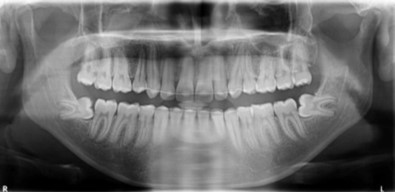

Radiographic assessment. The panoramic radiograph confirmed the presence of all permanent teeth with the presence of 18, 28, 38 and 48 tooth germs with normal alveolar bone levels. (Figure 2).

Figure 2.Pre-treatment panoramic radiograph

Pre-treatment panoramic radiograph